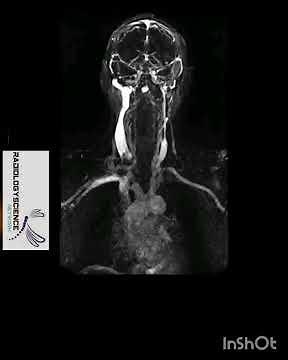

TWIST MRI or TRICKS

Radiologyscience Network: TWIST (Time-resolved angiography With Interleaved Stochastic Trajectories) is a time-resolved 3D MRA technique with very high temporal (sub-second) and spatial resolution (sub-millimeter) which will allow to capture the multiple arterial, mixed, venous phase images during the passage of a contrast agent through the ...

MRI TWIST BRAIN(Time-resolved angiography With Interleaved Stochastic Trajectories)MRA& MRV Contrast

MRI TWIST BRAIN(Time-resolved angiography With Interleaved Stoc

Tricks/Twist MRI Contrast Enhanced Angiography || Radiologicalscience